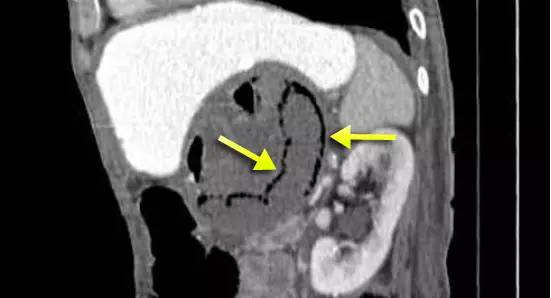

下图:疝入肠管坏死,形成壁间气肿(黄箭)。